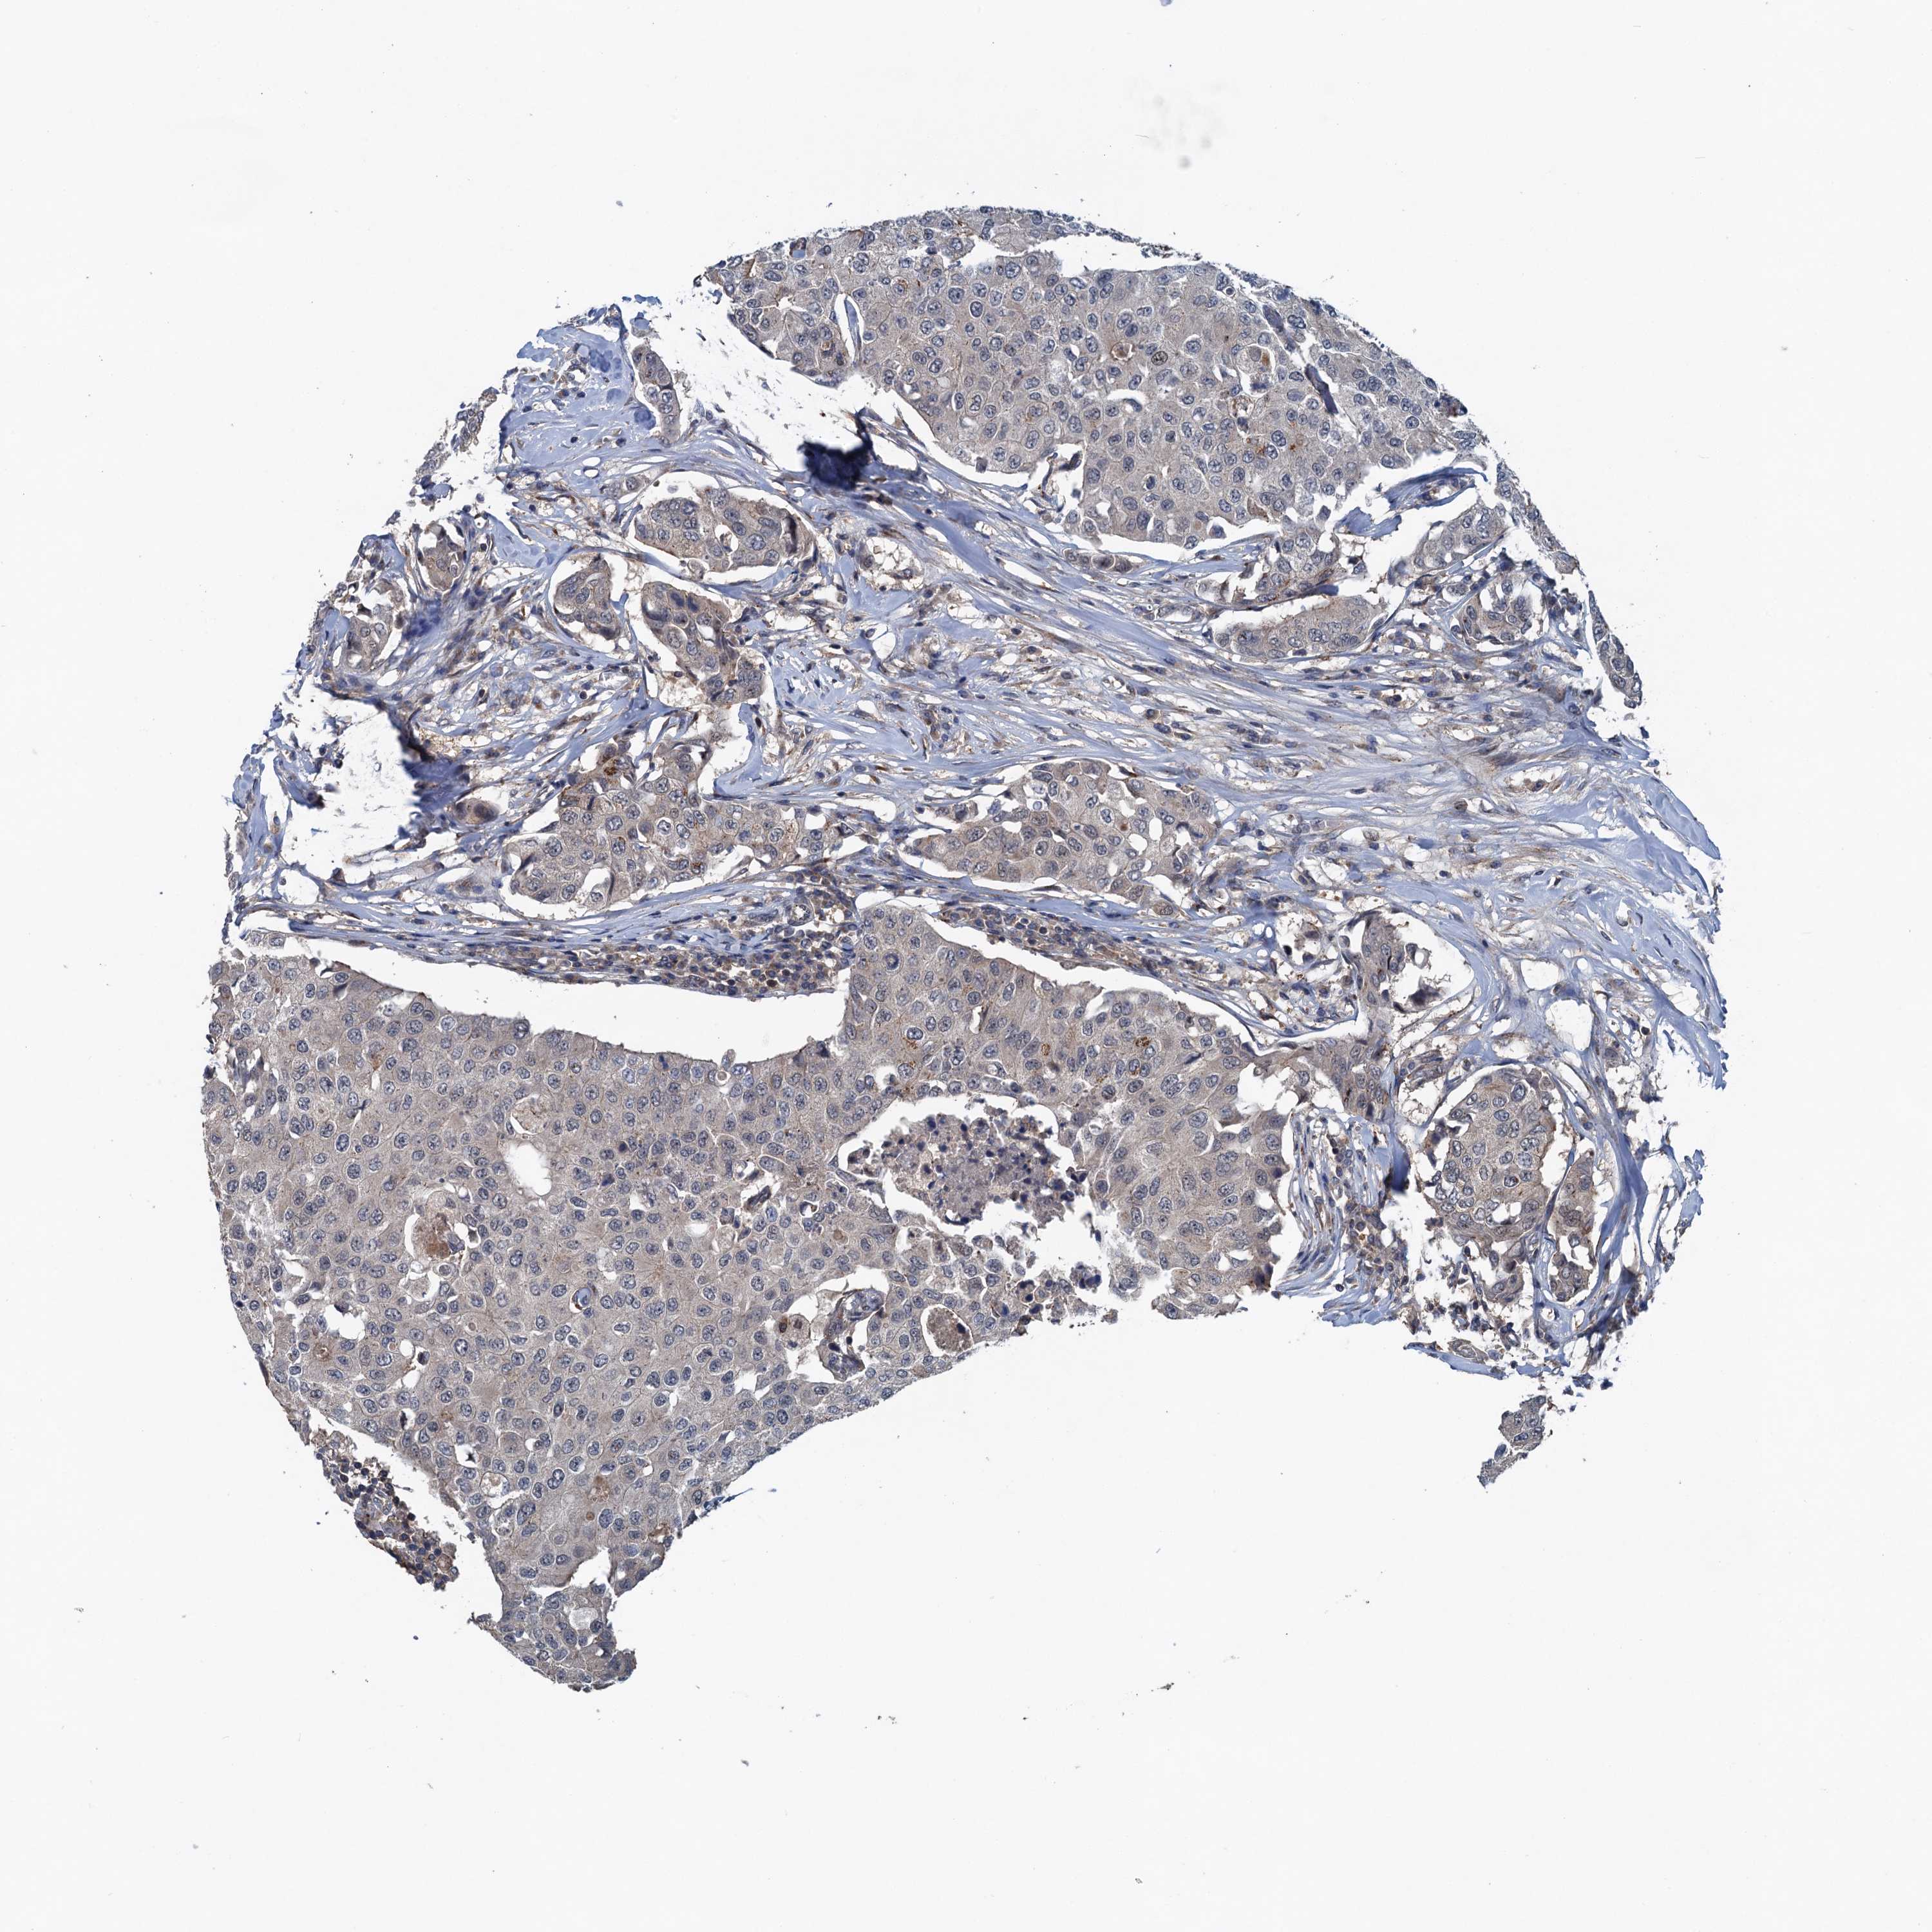

CANCER BREAST CANCER Show tissue menu

BRCA TCGA BRCA VALIDATION PROTEIN EXPRESSION